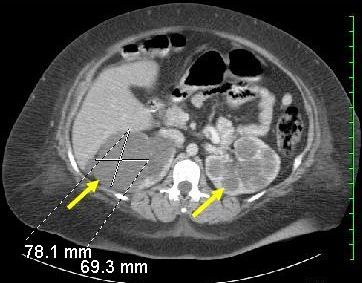

This CT scan of a 38-year-old woman shows innumerable cystic lesions in both kidneys, suggestive of polycystic disease. A diagnosis of autosomal dominant polycystic kidney disease was made based on the patient’s family history and imaging findings.